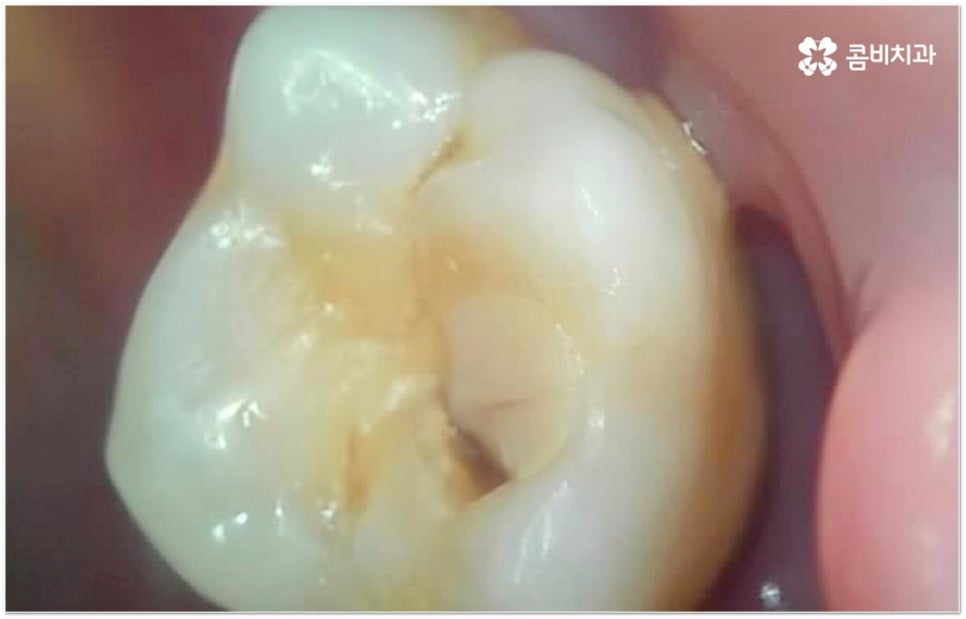

이때 누구나 겪는 과정이라는 생각에 대수롭지 않게 여기거나 무심하게 지나치는 분들도 있을 수 있는데 잇몸이 약해진 상태를 그냥 방치하게 되면 점차 악화되어 더 자주 붓고 피가 많이 나면서 퇴축도 빨라지고 (한 번 내려앉은 잇몸을 되돌리는 것은 거의 불가능합니다) 치주 질환이 심해지며 결국 치아를 상실하게 되는 결과로 이어질 수도 있기 때문에 주의하실 필요가 있어요. 잘 아시다시피 치아는 영구치 이후 탈락되면 다시 새롭게 나지 않는데 특히 성인 환자분들의 경우 치아 상실의 가장 주된 원인을 풍치에서 찾을 수 있는 만큼 잇몸 건강 관리를 잘 해 주는 것이 치아 상실의 위험에 대한 초기 대처 및 예방법으로 중요한 포인트라고 할 수 있습니다.

이와 같이 자연스러운 노화 또는 심각한 구강 질환이나 큰 외부의 충격으로 인해 치아를 잃게 되었다면 어떻게 해야 할까요? 치아는 음식물을 잘게 잘라 소화를 도와주는 저작 기능을 하므로 살아가는데 기본이 되는 동시에 전신 건강과도 밀접한 연관을 가지며 말을 할 때 정확한 발음을 할 수 있도록 도와주거나 얼굴 윤곽을 잡아주고 웃을 때 자연스럽게 보일 수 있도록 하는 심미적인 부분 또한 담당하기 때문에 만약에 치아를 상실하였다면 빠른 시간 안에 이를 대체해 주실 필요가 있는데요. 이를 수복해 줄 수 있는 방법에는 여러 가지가 있으나 현재 자연 치아와 가장 유사한 수준의 기능성과 심미성을 회복할 수 있는 방법으로는 임플란트 시술이 손꼽히고 있습니다.